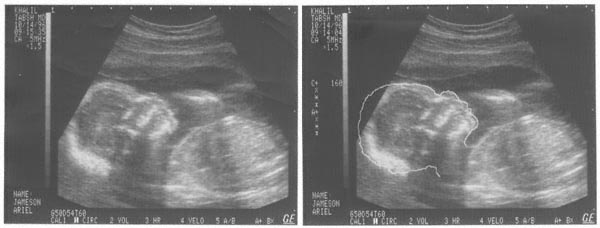

Baby Louis Sonogram These are sonograms of Louis at -22.5 weeks (17.5 weeks gestation). They are both the same image, but the second one has an outline of his profile drawn on it to highlight where his head is.

Click the photo for a bigger view.